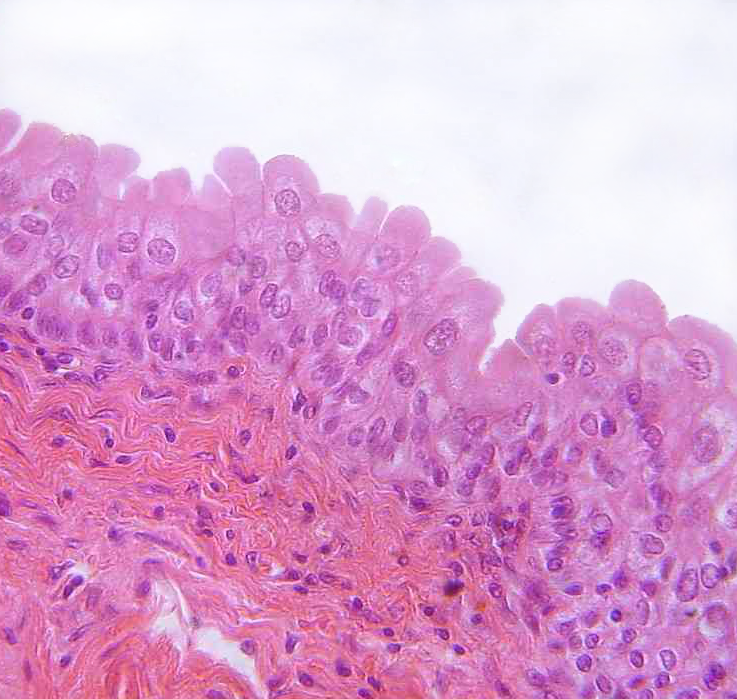

2. Stratified squamous

1. Found in the oral cavity, esophagus, vagina, and canal.